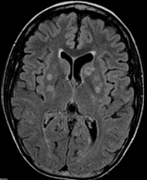

развитие ишемических очагов в головном мозгу.Церебральный аспергиллез. чаще

развивается как метастатический процесс из первичного очага поражения (легких,

орбит, околоносовых пазух), протекает в видеменингоэнцефалита, с последующей

окклюзиейинтракраниальных сосудов вплоть до инфаркта и абсцесса головного мозга

(Рис.15.). Аспергиллез головного мозга чаще проявляется нарушением сознания,головокружением,

тошнотой и рвотой, очаговой неврологической симптоматикой и головными болями.

Рисунок 15. Компьютерная томография очагов аспергиллеза

головного мозга.